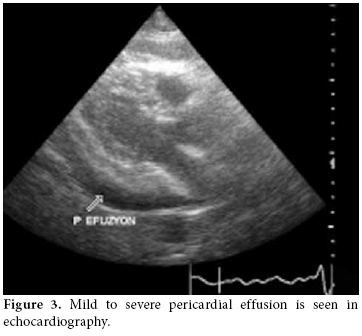

In high resolution computed tomography (HRCT) there was linear atelectasis, and fibrotic changes were found which were more pronounced in the upper lobes of both lungs (figure 2). Mild to severe pericardial effusion was seen in echocardiography (ECHO; figure 3). Three days after 20 mg intravenous prednisolone therapy, fluid accumulation was considered to be gradually decreasing in ECHO (figure 4).